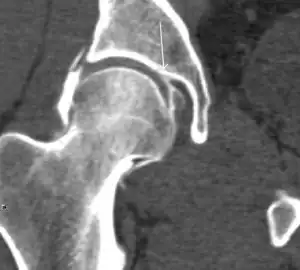

Most of the angles and measurements described in the plain radiograph section can be accurately reproduced on MRI. In addition, the superiority of MRI resolution with intra-articular contrast allows detection of labral and chondral abnormalities that may influence the choice of medical, percutaneous, or surgical management (Figure 9).[1]

Figure 9:

-

Sagittal T1 weighted image showing anterosuperior labral tear.[1] -

Sagittal T1 weighted image showing chondral lesion.[1] -

Sagittal CT-arthrography showing posteroinferior chondral injury.[1] -

Coronal CT-arthrography (d) showing ligamentum teres tear.[1]

MR arthrography has proven superior in accuracy when compared to native MR imaging. It is considered the best technique to assess the labrum. Knowledge of the normal variable morphology of the labrum helps to differentiate tears from normal variants. A triangular shape is most commonly seen in 66% of asymptomatic volunteers, but round, flattened, and absent labra can also be found in asymptomatic populations. MR arthrography has demonstrated sensitivity over 90% and specificity close to 100% in detecting labral tears. Loose bodies are demonstrated as filling defects surrounded by the hyperintense gadolinium.[1]

Association between labral tears and chondral damage has been demonstrated. This underscores the interaction between cartilage and labrum damage in the progression of osteoarthritis. Chondral damage to the posteroinferior part of the acetabulum as a contrecoup lesion occurs in approximately one-third of pincer cases secondary to persistent abutment on the anterior part of the joint leading to a slight posteroinferior subluxation. This is considered a bad prognosis sign.[1]

MR arthrography can also demonstrate ligamentum teres rupture or capsular laxity, which are debated causes of microinstability of the hip. Elongation of the capsule or injury to the iliofemoral ligament or labrum may be secondary to microtrauma in athletes. MR can demonstrate abnormalities in these cases, such as increased joint volume or a ligamentum teres tear (Figure 9).[1]